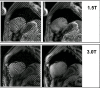

There are advantages to conducting cardiovascular magnetic resonance (CMR) studies at a field strength of 3.0 Telsa, including the increase in bulk magnetization, the increase in frequency separation of off-resonance spins, and the increase in T1 of many tissues. However, there are significant challenges to routinely performing CMR at 3.0 T, including the reduction in main magnetic field homogeneity, the increase in RF power deposition, and the increase in susceptibility-based artifacts.In this review, we outline the underlying physical effects that occur when imaging at higher fields, examine the practical results these effects have on the CMR applications, and examine methods used to compensate for these effects. Specifically, we will review cine imaging, MR coronary angiography, myocardial perfusion imaging, late gadolinium enhancement, and vascular wall imaging.